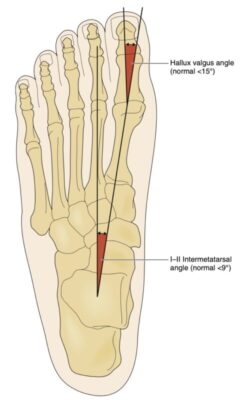

Hình ảnh học

Phim chụp X quang đơn giản chịu trọng lượng sẽ cung cấp hầu hết các thông tin cần thiết. Hình chụp trước sau (Hình 3) thể hiện góc (Hình 4) giữa xương bàn chân thứ nhất và thứ hai (góc giữa các xương bàn chân). Cũng cần đánh giá dấu hiệu thoái hóa khớp bàn ngón thứ nhất.